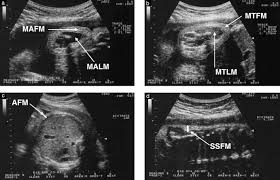

Twin pregnancy scans

Twin pregnancies require more frequent and specialized ultrasound monitoring compared to single pregnancies. Scans are crucial for determining chorionicity (whether twins share a placenta)